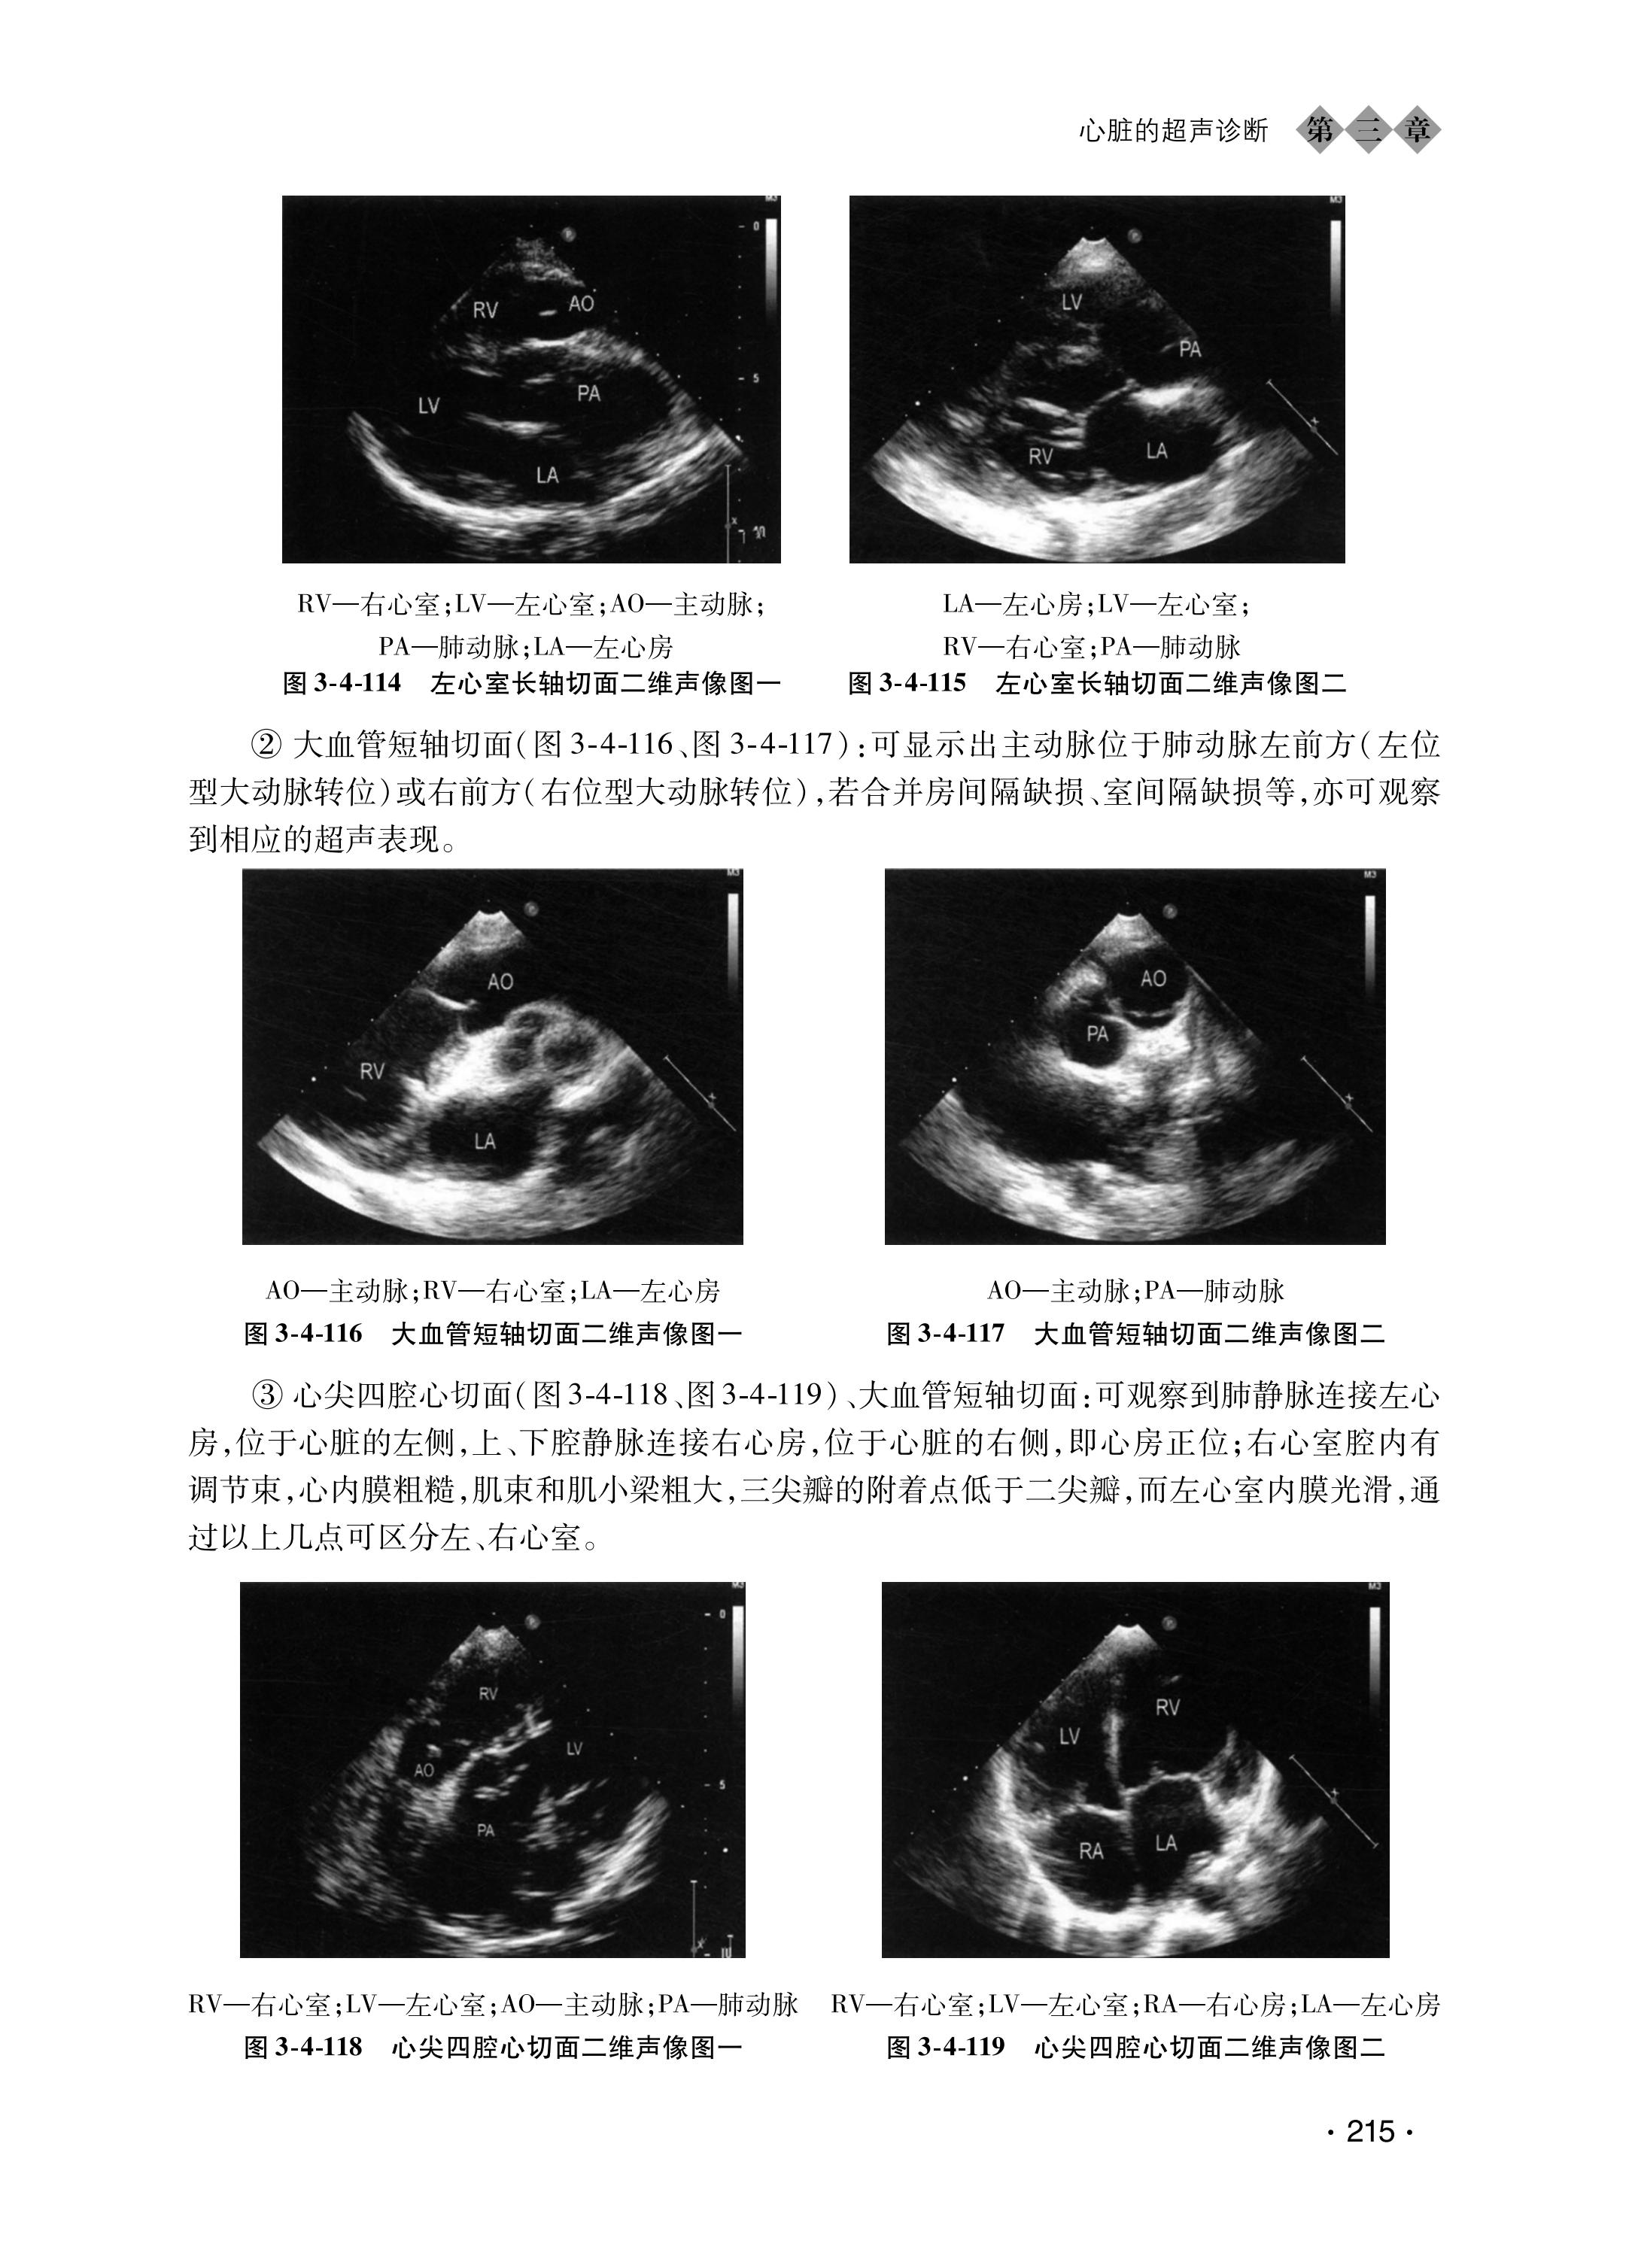

心脏常见疾病的超声诊断